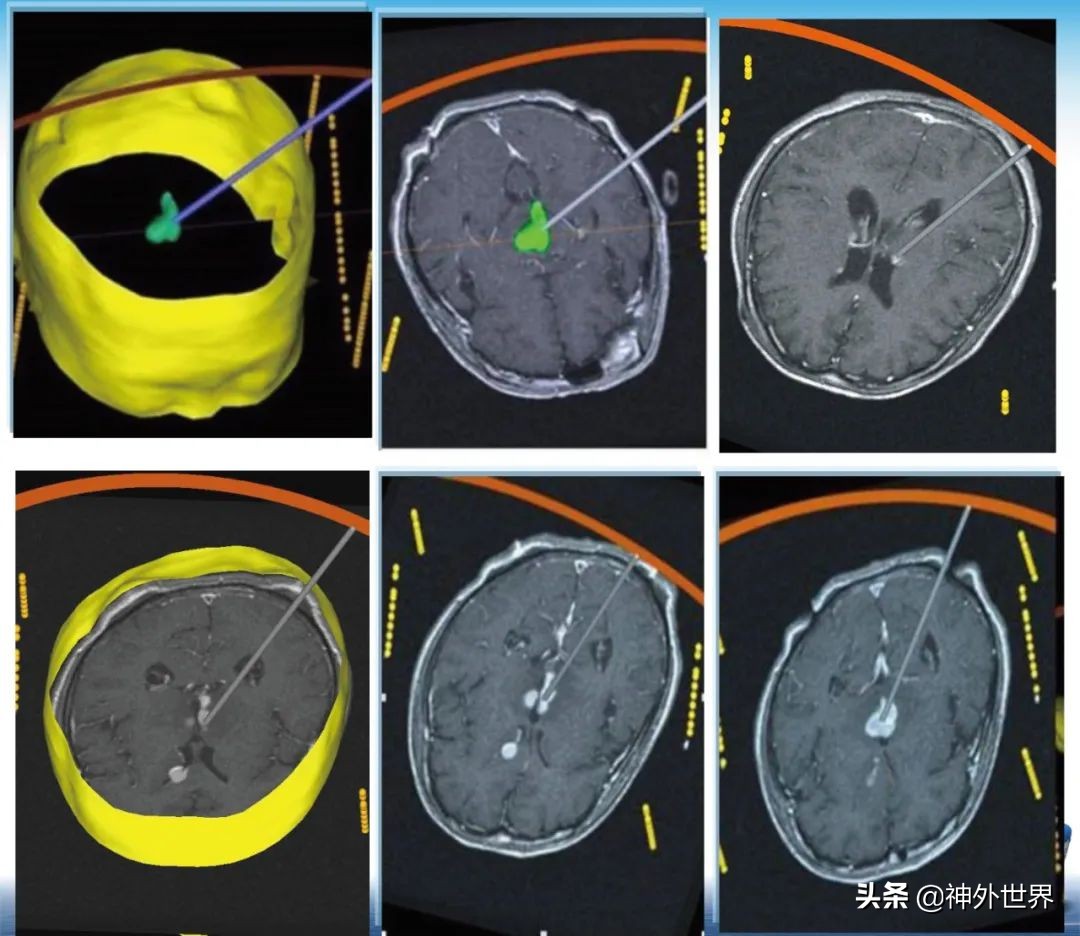

专业方向:颅内肿瘤的显微外科手术切除,颅咽管瘤综合治疗具有特色;在立体定向脑内病灶活检、立体定向清除脑干血肿、立体定向间质内放疗、机器人辅助神经外科手术方面具有专长。